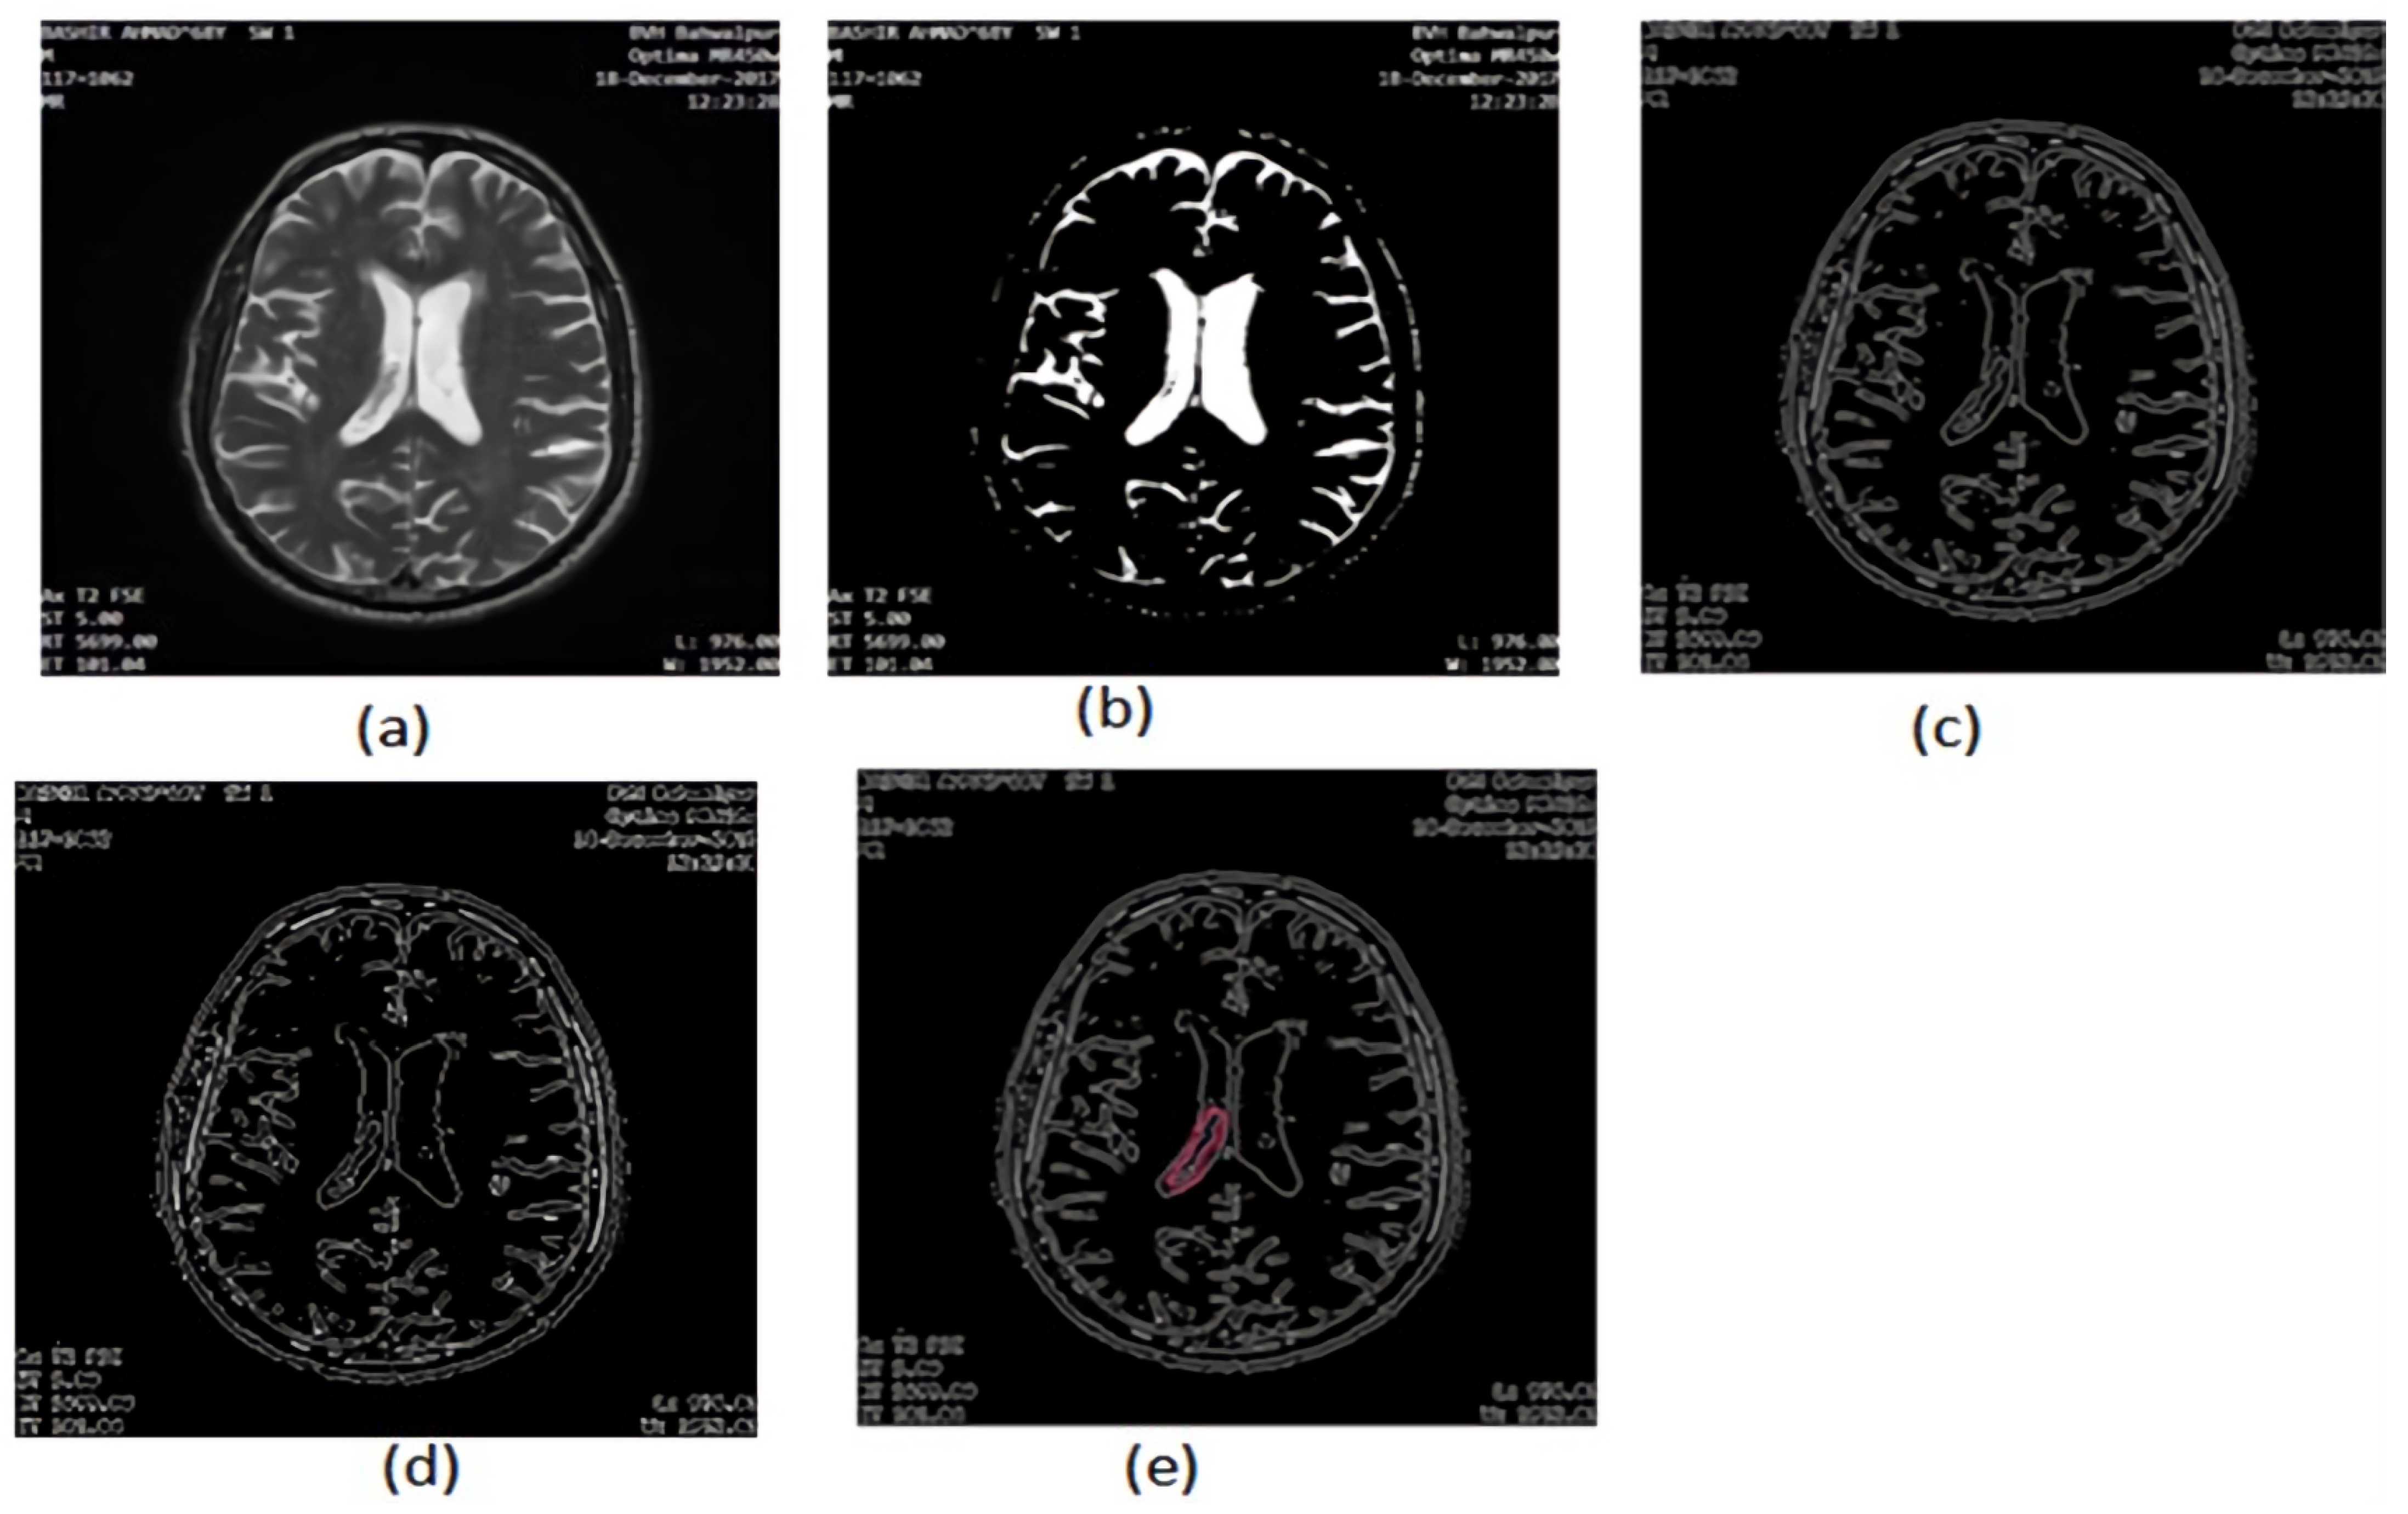

2.2.7. Area Segmentation using Watershed Algorithm

2.2.8. Region Masking and the Separation

2.3. Proposed a Colorized Method for Masked Area Colorization